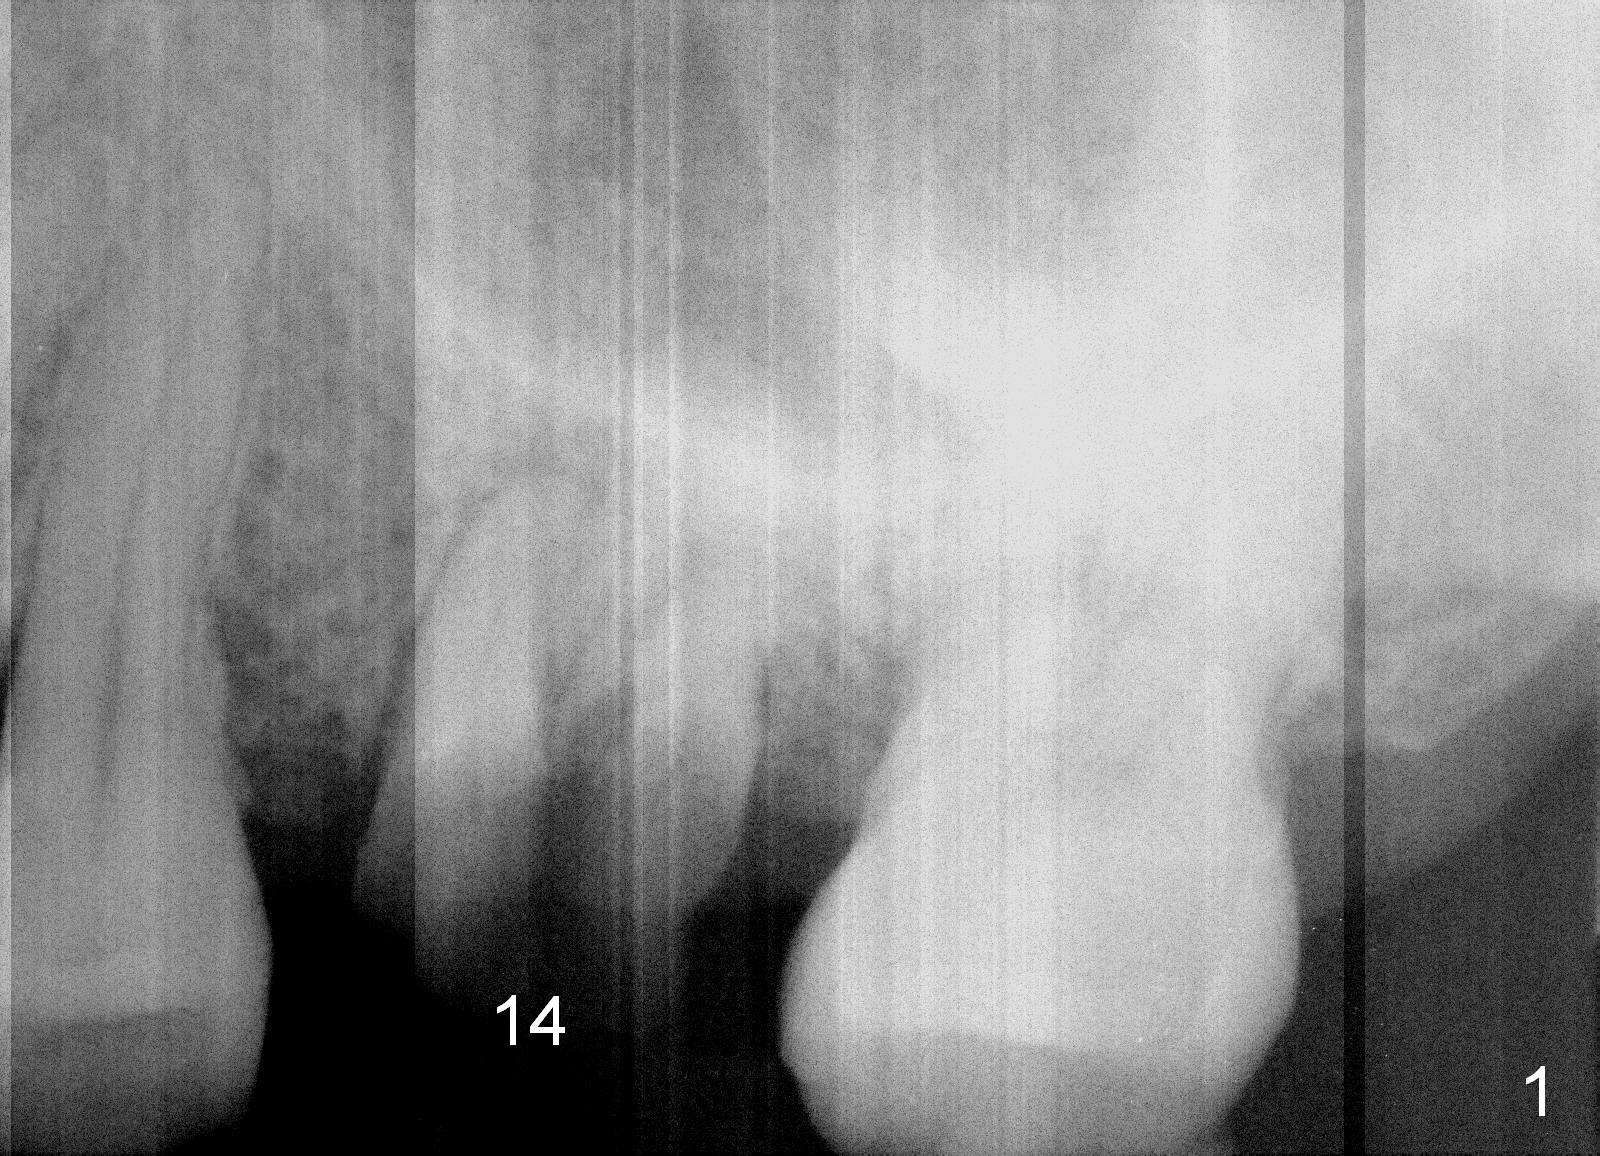

A 49-year-old man requests to restore #14 with residual roots (Fig.1). There is periapical radiolucency (Fig.2 *). A 5.9x10 mm bone-level implant is placed with minor sinus lift (Fig.3), whereas a short (Fig.4) or long (Fig.5) tissue-level implant is placed without or with sinus lift. The implant could be as large as 7 mm (Fig.5) to prevent post-extraction ridge atrophy.